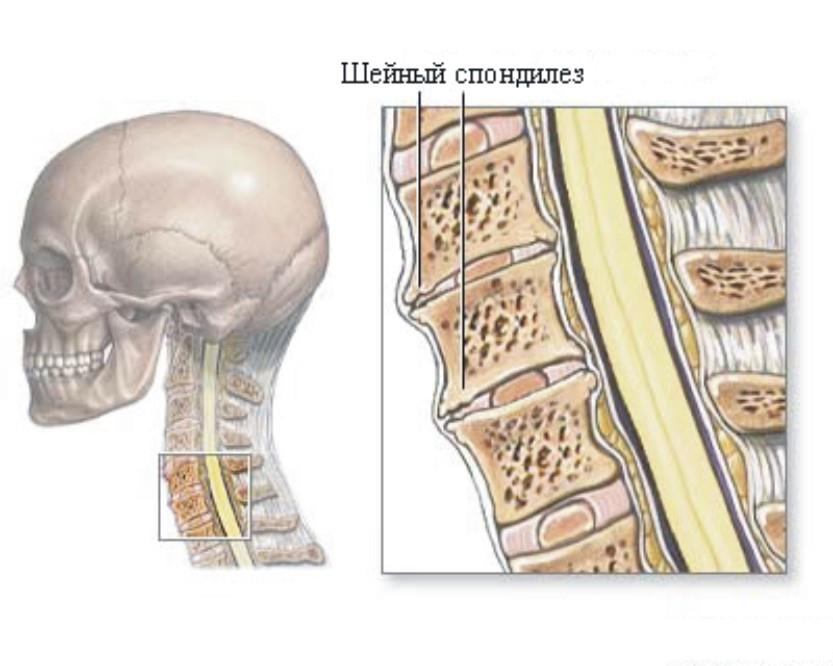

Поражение межпозвоночных суставов по своей сути ничем не отличается от остеоартроза в суставах конечностей. Но, учитывая течения болезни, врачи выделяют это заболевание, обозначая его как остеохондроз. Очень близко к этому состоянию и такой диагноз как шейный спондилез. При остеохондрозе поражаются и другие образования позвоночника – прежде межпозвонковые диски, структура которых значительно отличается от строения суставов конечностей. При остеохондрозе могут поражаться любые отделы позвоночника – шейный, грудной, поясничный. В принципе, остеохондроз - это плата за прямохождение. Ни один из четвероногих не страдает этим недугом.

Шейный спондилез

Спондилёз развивается в результате физических перегрузок или травматизации позвоночника. Чаще встречается у лиц пожилого возраста.

Что происходит?

При шейном спондилезе происходит разрастание клювовидных и шиповидных остеофитов по краям тел позвонков. Некоторые неправильно трактуют остеофиты как "отложение солей", но это определение неправильное, поскольку процесс развития остеофитов связан с костным перерождением связок. Чаще всего спондилез является следствием возрастных изменений (чаще в шейном отделе). С распространением профессий умственного труда число лиц, страдающих от боли в шее, боли в плече возросло.